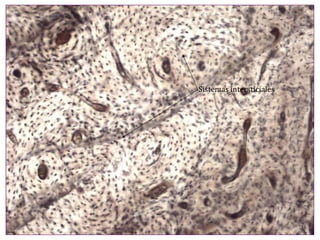

El documento describe diferentes aspectos de la histología del cartílago y el hueso, incluyendo las estructuras del cartílago como condroblastos, matriz y lagunas, y las estructuras óseas como conductos de Havers, osteoblastos y osteoclastos. También describe las etapas de la osificación endocondral, el proceso por el cual el cartílago se transforma en hueso, incluyendo las zonas de cartílago en reposo, proliferación, hipertrofia, erosión y osificación.